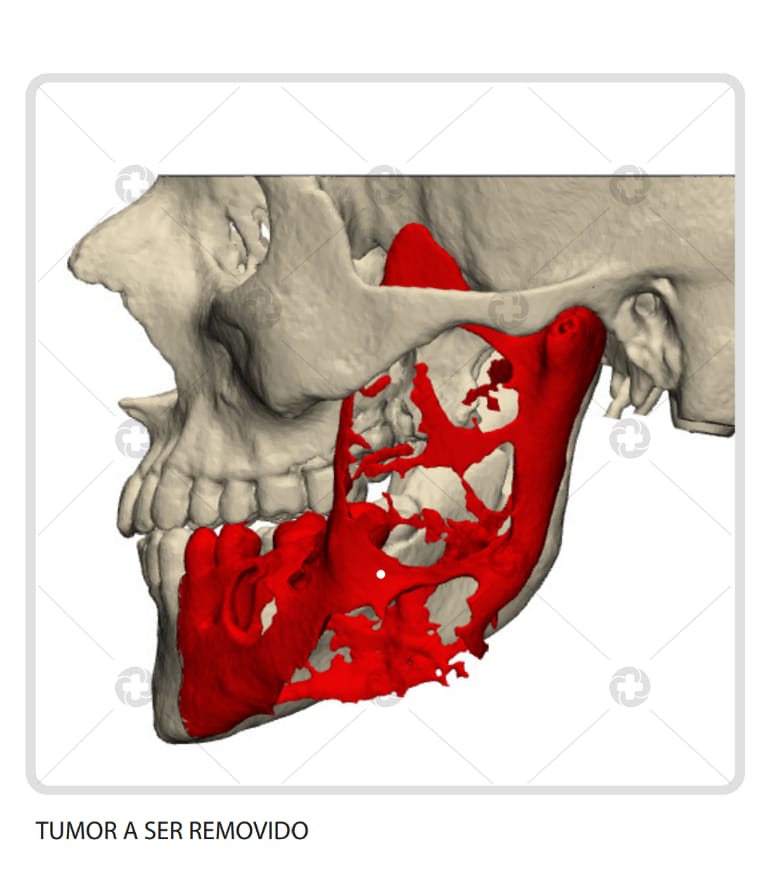

A cirurgia inédita consistiu na remoção do tumor “ameloblastoma”, um tumor agressivo, porém benigno, envolvendo estruturas nobres, como mandíbula e ATM. Com isso, foi feita a reconstrução com prótese customizada das duas estruturas perdidas, sendo a prótese em titânio.

O procedimento devolveu a função ao paciente, um adolescente de 17 anos, que sofria de dores frequentes, afetando diretamente a mandíbula direita.

A realização do procedimento foi inédita na rede de saúde do Estado e na região Norte.